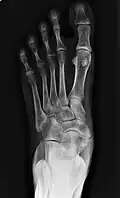

![]() X-ray of the foot showing an accessory navicular bone | |

An accessory navicular bone is an accessory bone of the foot that occasionally develops abnormally in front of the ankle towards the inside of the foot. This bone may be present in approximately 2-14% of the general population and is usually asymptomatic.[1][2][3] When it is symptomatic, surgery may be necessary.